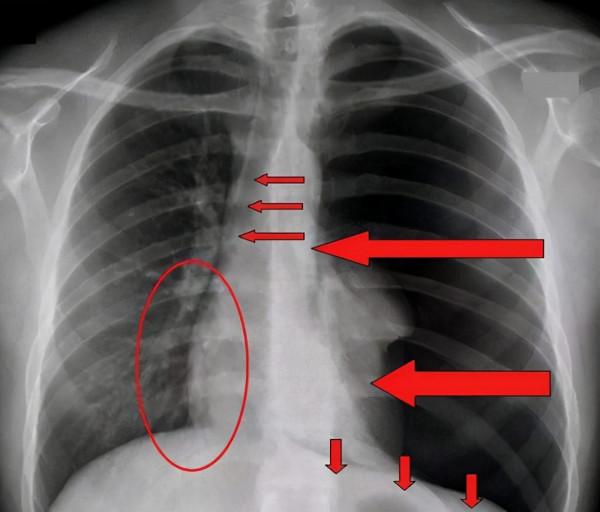

現在各地高校都陸續放假,很多學生也是積極配合疫情防控,安全回家。但是我們最近接到某高校的一個大學生,因為胸部疼痛劇烈,緊急求醫。經過了解診斷,男生為氣胸,很多氣泡已經跑到肺裡,有肺破裂的風險。

生活中遇到氣胸的並不少見,最典型的就是長期情緒控制不住,大量怒氣導致胸腔過多積氣,嚴重會導致胸腔氣壓過大,導致肺膜破裂,也會危及生命。而這個男生是什麼原因導致的氣胸,說出來你可能不信,但很多人都存在類似的情況,在此醫生提醒,一定要引起重視。